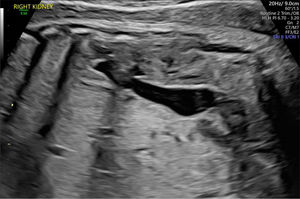

Displasia obstructiva (fig. 2).

Figura 2.Displasia obstructiva alrededor de las 20 semanas de edad gestacional. Este feto masculino mostraba una obstrucción del tracto urinario inferior con riñones ecogénicos e hidrouréter severo; en esta imagen se visualiza y mide el riñón derecho. Imagen ecográfica del Centro Médico de la Universidad Erasmus.